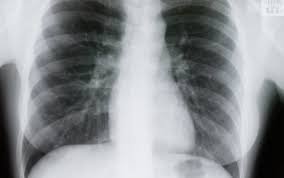

Ai avut COVID și crezi că ai trecut cu bine peste boală? Medicii avertizează: trebuie făcute două investigații după vindecare